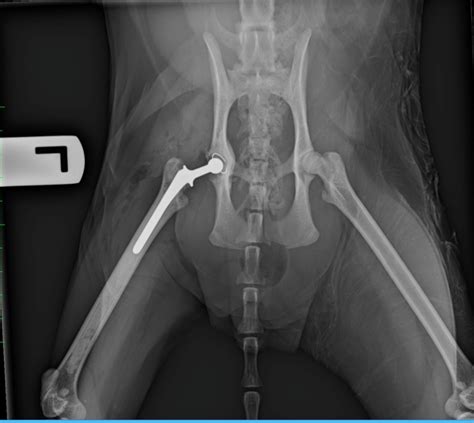

Jami Lance Blog